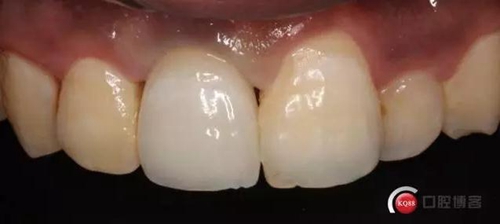

兩個月后

兩月后牙齦恢復(fù)正常穩(wěn)定。正式取模,E.max鑄瓷修復(fù)

可以看出牙齦袖口很漂亮,修復(fù)體外形也不錯,就是顏色偏白一點,讓患者改色,患者覺得已經(jīng)很滿意了,而且考慮其他牙以后做美白,所以不換了。

可以看出修復(fù)體的邊緣密合度都很好。希望這次修復(fù)能夠讓這顆牙多服役幾年吧